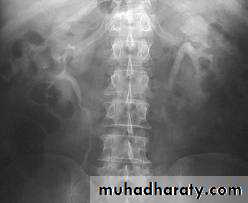

- Over 90% of calculi are radiopaque on plain films and virtually all on CT as very sensitive for detection of calculi, even those that appear radiolucent on plain film.- Most of these stones are a mixture of calcium oxalate and phosphate.

Ddx of stone on KUB :

1. Gall stone2. Calcified LN , cartilage ,fibroid,

3. Phlebolith: round, lucent centre.